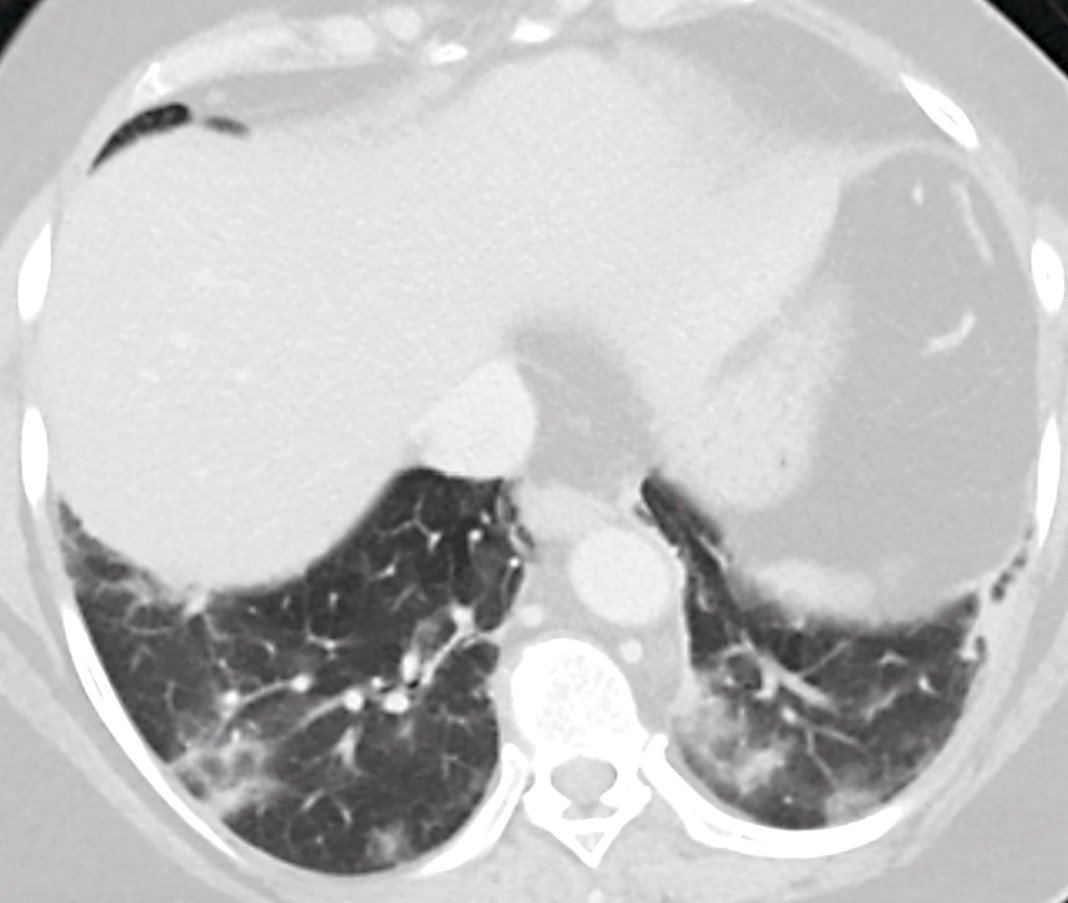

Det ble rekvirert en ultralydundersøkelse av lever og galleveier, men ettersom pasienten var overvektig og flere radiologer var i karantene på grunn av den pågående koronaepidemien, valgte man å endre dette til en CT-undersøkelse med intravenøs kontrast. Ved CT av abdomen og bekken ble det ikke påvist aktuelle funn i buken, utenom gallestein som var kjent fra tidligere. Det var ingen radiologiske tegn på kolecystitt. På basale lungesnitt ble det imidlertid sett løst mettede fortetninger perifert i begge lunger samt enkelte områder med mer konsolidert preg. Det var ingen pleuravæske. Radiologen vurderte at funnene kunne passe med viral eller atypisk pneumoni (figur 1).

Enkelte pasienter med covid-19 debuterer imidlertid med andre symptomer. I løpet av de siste to ukene har vi i vårt akuttmottak hatt ytterligere fem pasienter med tilsvarende symptombilde, der covid-19 har blitt bekreftet ved sanntids-PCR. Det dominerende symptombildet hos alle disse var magesmerter, der enkelte også hadde smerter i nedre del av buken. I tillegg rapporterte de om nedsatt matlyst, kvalme og oppkast. Noen hadde også diaré. Ingen hadde nytilkomne luftveissymptomer. Alle ble utredet med CT abdomen som ledd i utredningen av magesmerter, der bildene viste typiske funn for covid-19 i lungene (figur 2).